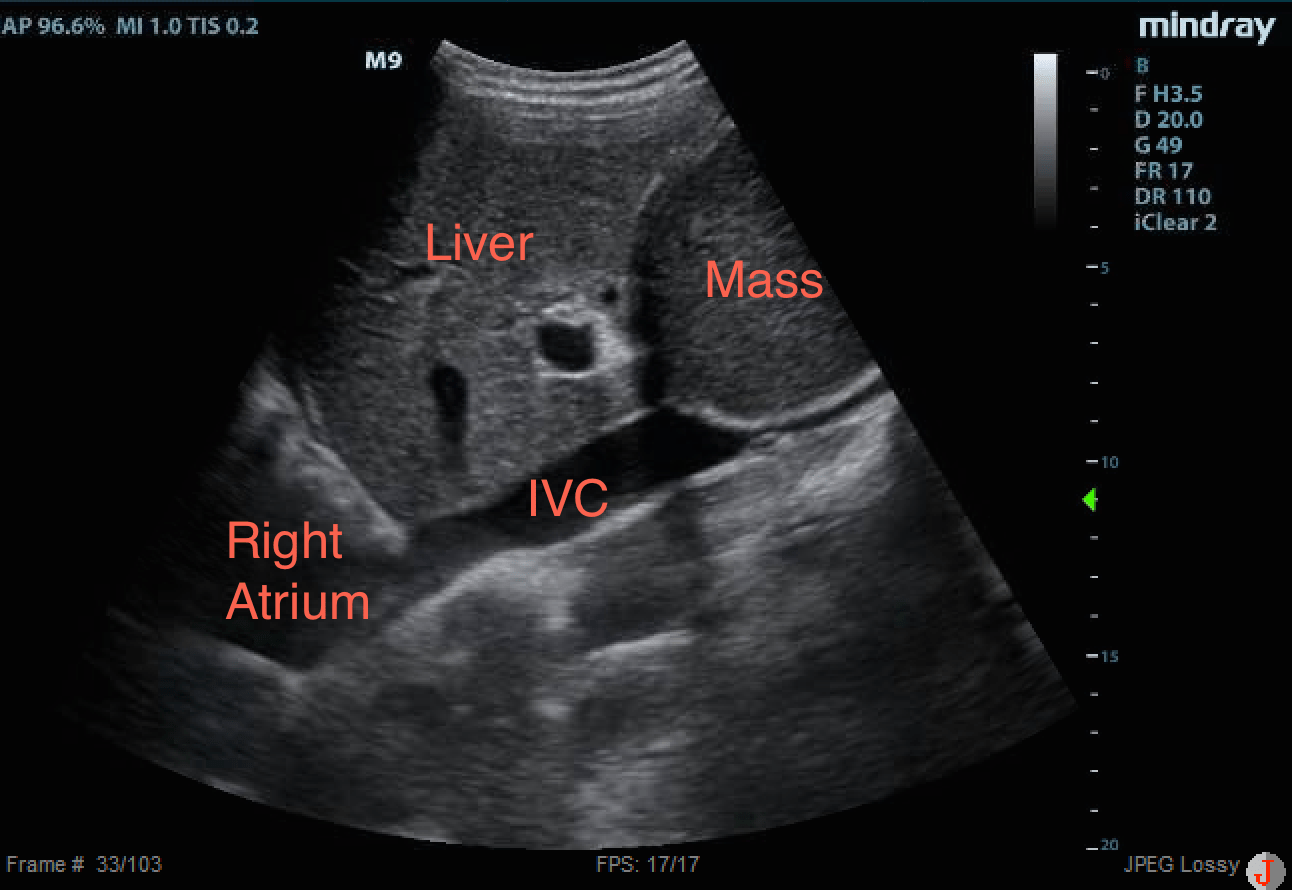

This was investigated more:

There is a homogenous mass seen adjacent to the liver, compressing the IVC.

Could the cause of her syncope be obstruction of venous return to the heart?